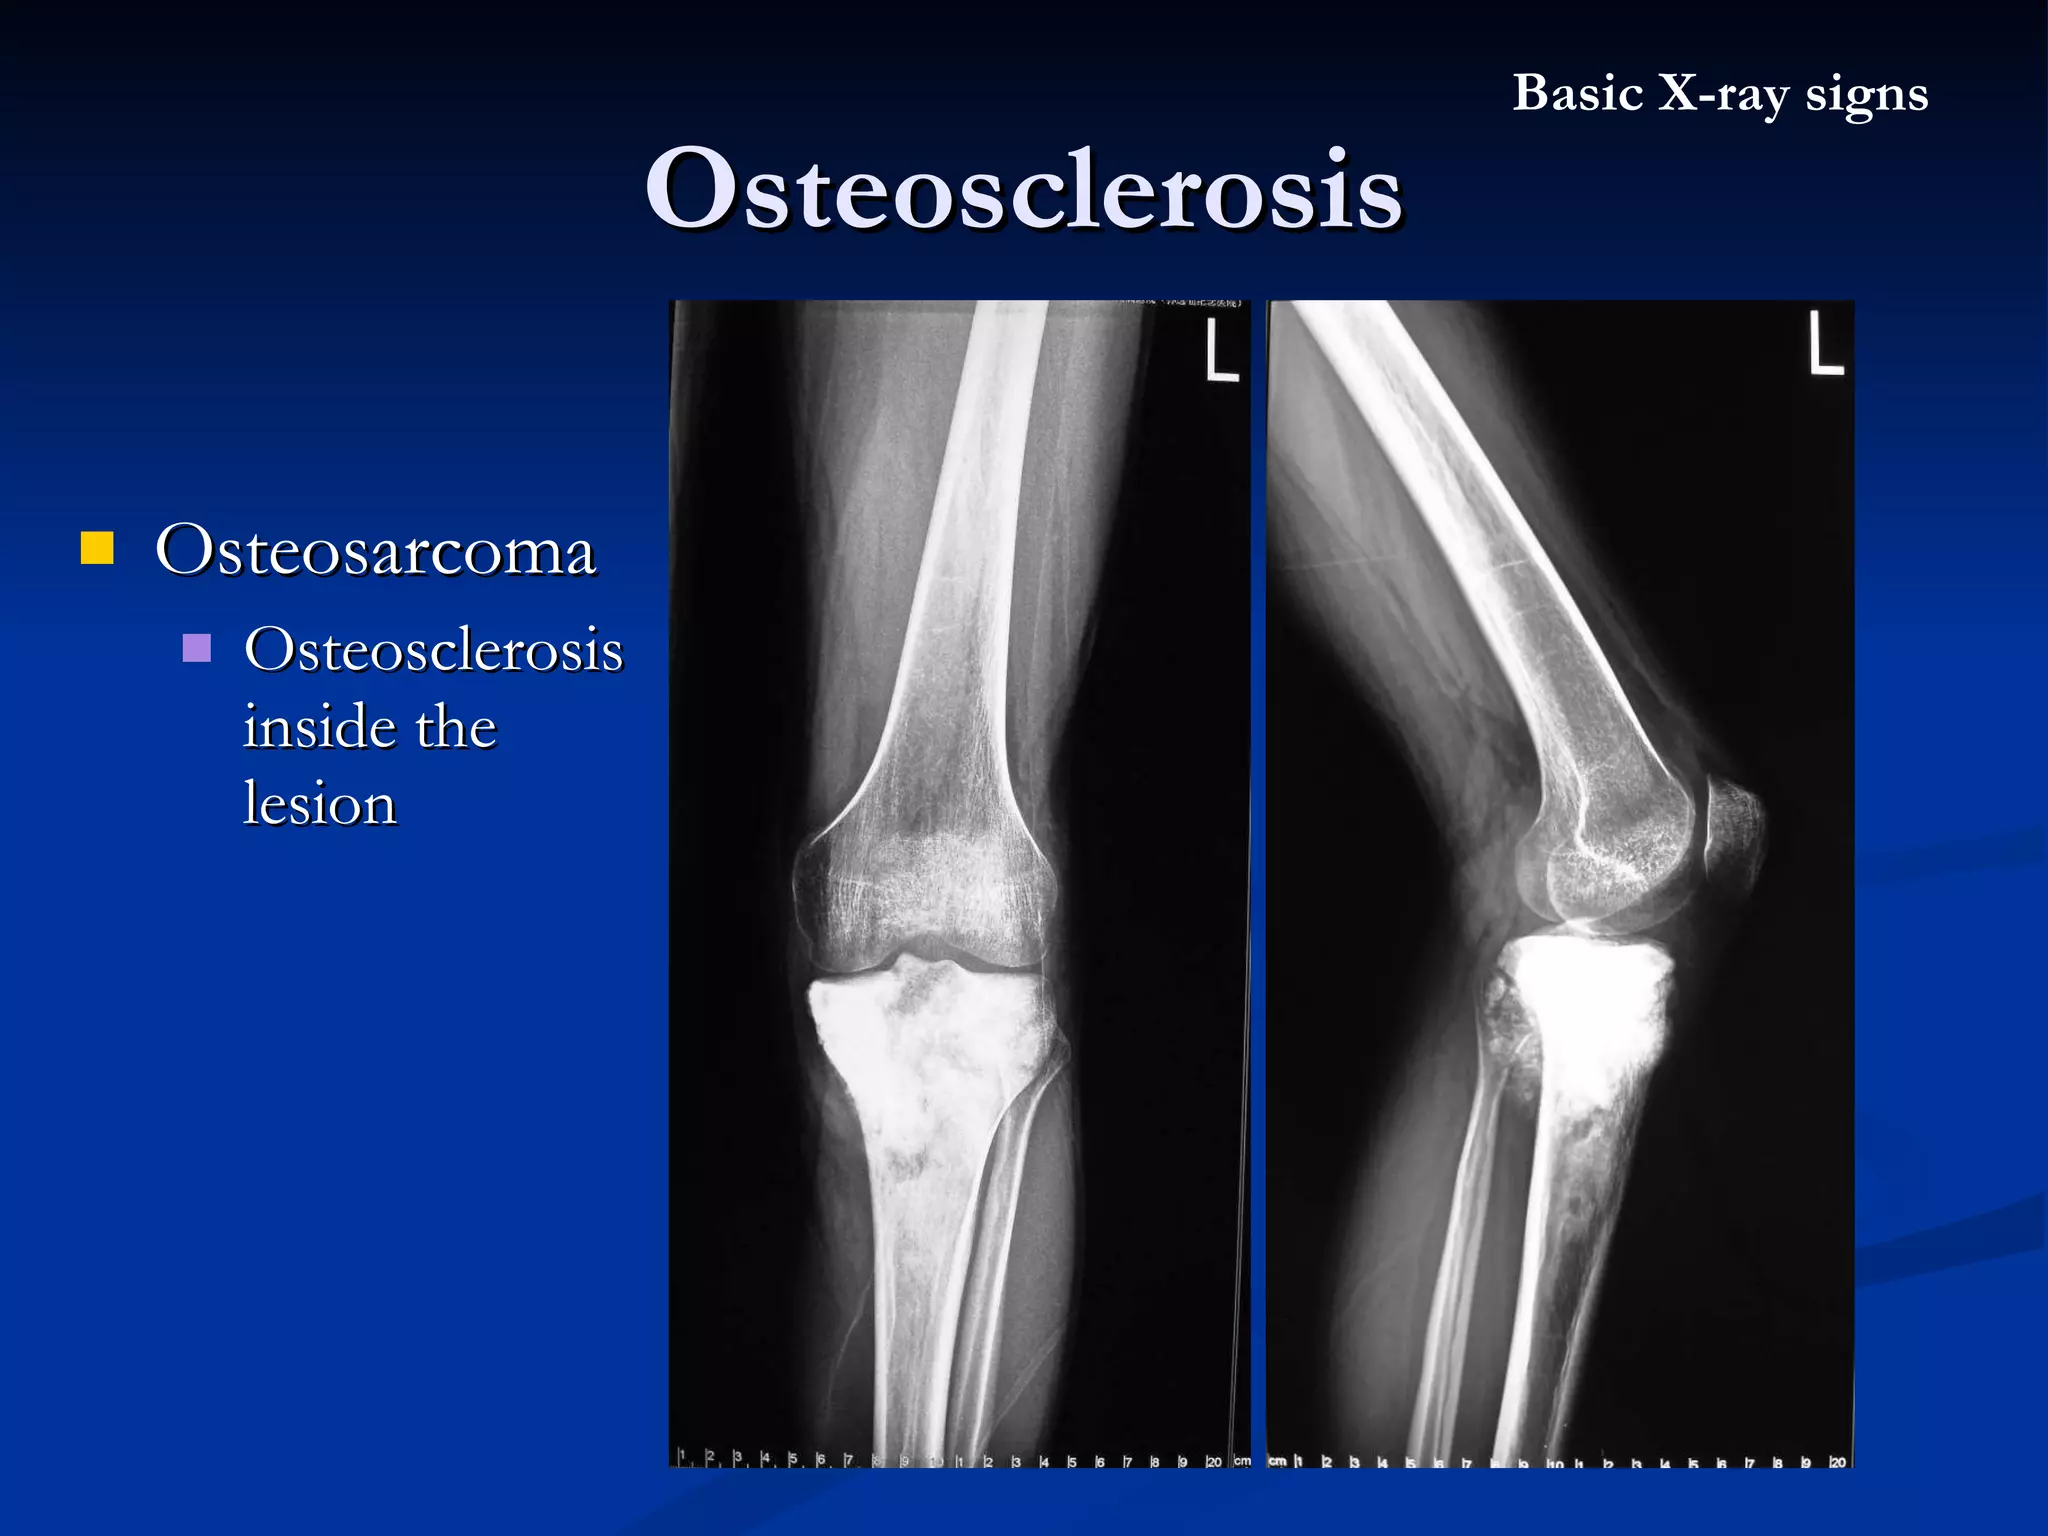

Osteosarcoma  Osteosclerosis inside the lesion Osteosclerosis Basic X-ray signs

Osteosarcorma  Osteosclerosis inside the lesion Periosteal reaction Osteosclerosis Basic X-ray signs